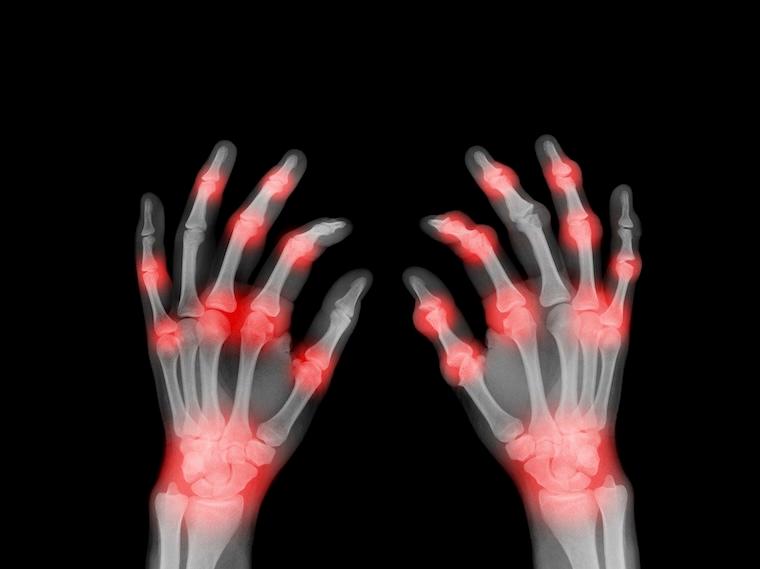

Rheumatoid arthritis is a chronic inflammatory condition that can damage joints.

Researchers have discovered how “leaky” mitochondria – the powerhouses of our cells – can drive harmful inflammation responsible for diseases such as lupus and rheumatoid arthritis. Scientists may be able to leverage the findings to develop better treatments for those diseases, improve our ability to fight off viruses and even slow aging.